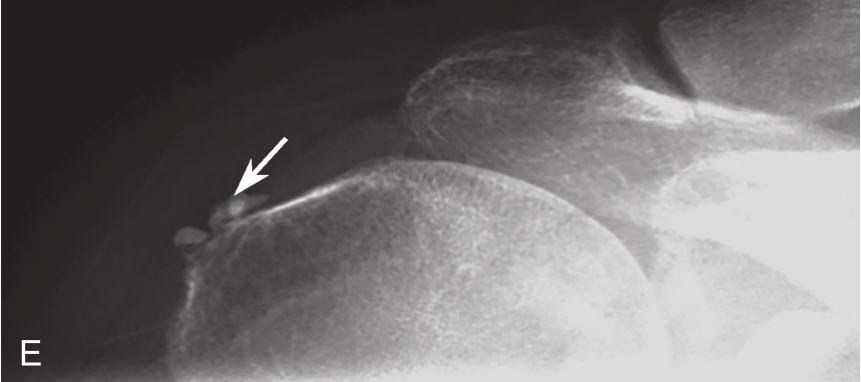

对物理治疗和口服药物治疗无效的钙化性肌腱炎,可行超声引导下钙化灶冲洗抽吸治疗,缓解疼痛和改善患者的活动功能。吸收期的钙化灶往往无明显声影,呈弱回声或稍强回声(图 2-2-1)。

▲ 图2-2-1 钙化性肌腱炎超声图

星号:钙化灶;箭头:肩峰下-三角肌下滑囊;Del:三角肌;SUP:冈上肌腱;HH:肱骨头